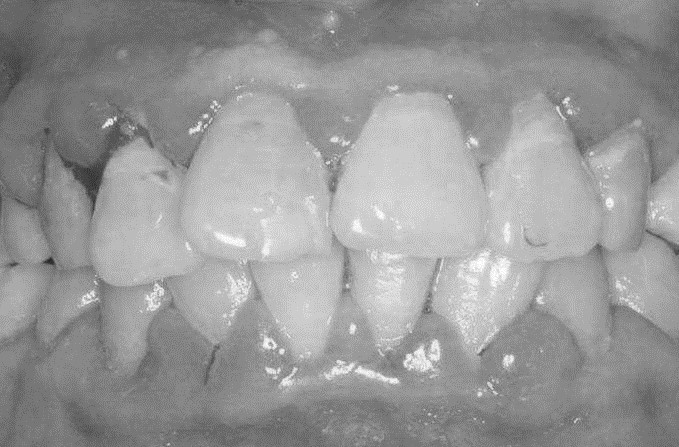

患者,女,52歲。因刷牙出血前來就診。自述刷牙時牙齦出血2年余,有時吃蘋果,饅頭等食物時牙齦出血,近1個月早晨起床偶有唾液中帶紅色血絲。曾作常規(guī)血象檢查,未見異常。無咬合不適或牙齒松動。檢查可見全口牙石(+),有大量菌斑堆積,全口牙齦齦緣中度充血,齦乳頭充血腫大,探診出血明顯,但無附著水平喪失,牙齒無松動,咬合關系未見異常。X線片顯示全口牙槽骨無明顯吸收。檢查結果如下圖:

(3)口腔檢查:全口牙石(+),大量菌斑堆積,全口牙齦齦緣中度充血,齦乳頭紅腫,探診出血。

(4)無附著喪失,牙齒無松動,咬合關系正常。

(5)X線片顯示全口牙槽骨無明顯吸收。